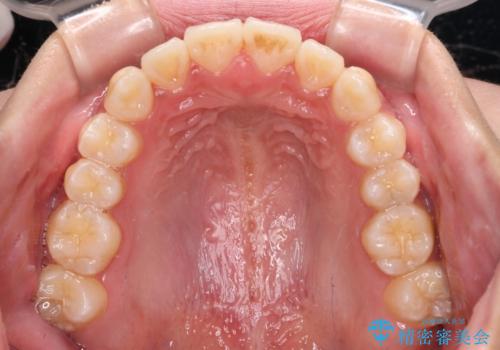

受け口と開咬を急速拡大装置とワイヤー装置で改善

舌の突出癖が開咬の原因であったので、改善のための舌トレーニングを行っていただきました。

舌トレーニングは後戻りにも大きく影響するため、とても重要なトレーニングです。